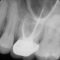

Dental CrownsDental Crowns -

When Do You Need a Crown?

Dental crowns are used when more conservative dental restorations cannot be used to improve the strength or appearance of a damaged tooth. Your dentist will determine what procedure you are eligible for based on your existing dental health and the aesthetic and functional benefits of a restorative dentistry treatment. The following are common reasons dental crowns are used to restore teeth:

Before & After Crown Photos

Here are some examples of recent work we completed for a current patient. These images include before and after photos of the work. The images are placed over one another to better represent the improvement after completion.